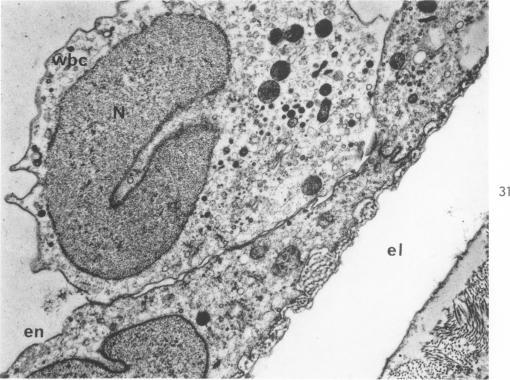

HESS R, STAEUBLI W

Am J Pathol. 1963 Sep;43(3):301-35.